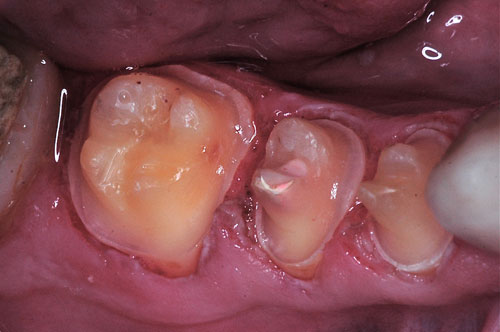

Comenzamos desmontando los sectores posteriores, lo que constituye un camino a la inversa de como se debe montar una Rehabilitación Oral.

Comenzamos por el sector superior derecho, instalando nuestros provisorios del sector y ganando la mitad del espacio creado en el articulador.

(Nótense los mini desgarros gingivales producto de un tallado infragingival por alisado radicular, con la consecuente retracción de encía a fín de que el borde cavo superficial de la preparación racional . termine siendo supragingival para facilitar el cepillado)